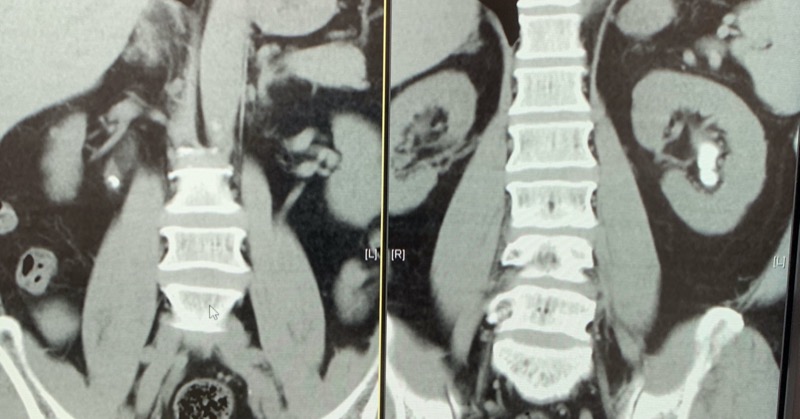

我馬上安排趙先生做電腦斷層掃描,放射科很快速的安排好一系列掃描片子,這顆隱藏於身體後腹腔、並卡在右側輸尿管的小石頭,終於無所遁形!

趙先生一時難以釋懷為什麼之前做的檢查沒有看出這顆小石頭!我解釋說明這是少見的隱藏版結石,深藏不露,一般X光不易察覺,又剛好沒有完全阻塞輸尿管,所以超音波檢查才會漏網。